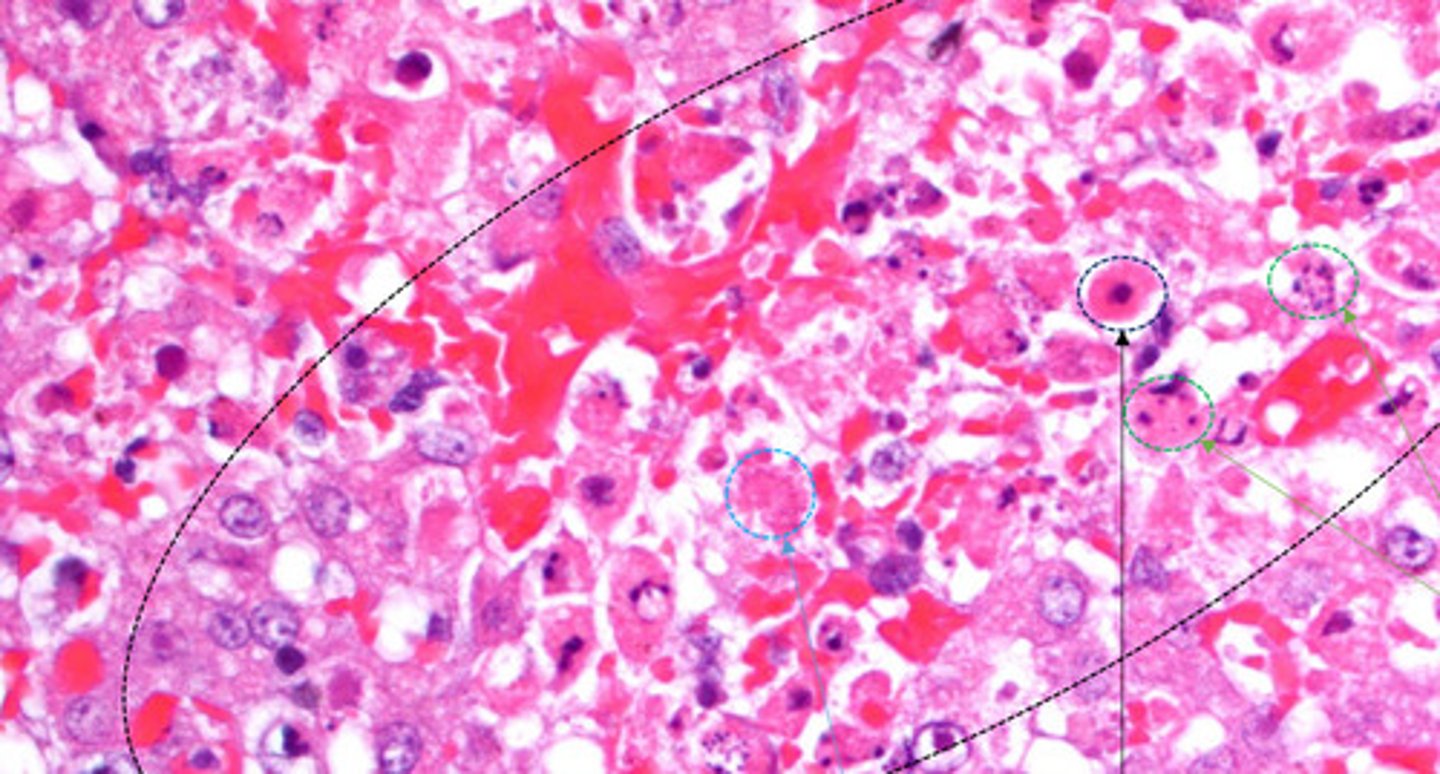

pyknosis

Identify the black circle?

Karyorrhectic cells

Identify the green circle?

karyolytic cells

Identify the Blue circle?